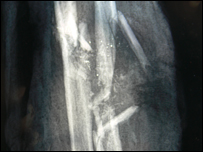

Còn sau đây là lời kể của Huỳnh Văn Hưng, 26 tuổi, từ xóm 2, thôn Phước Thiện, xã Bình Hải, Bình Sơn, Quảng Ngãi: Khi bị tàu Trung Quốc bắn, lúc đó anh đang làm gì? Huỳnh Văn Hưng: Chiều hôm bị bắn, gió rất lớn, thuyền của tụi tôi vào gần phía đảo để nấp gió thì thấy tàu của quân đội tiến ra. Vì thấy lính mặc đồng phục và trang bị súng nên sợ và bỏ chạy. Ông ba Là (chủ tàu) kéo neo chạy được một đoạn thì người ta bắn. Thấy thế, sợ quá, tụi tôi vào trong khoang máy để nấp. Năm sáu anh em ngồi co cụm lại một chỗ. Sau đó, tụi tôi bị bắn bị thương. Thấy tụi tôi bị thương, chủ tàu cho thuyền chạy xông vào đảo của người ta để cứu chữa vì nếu không làm vậy, có vấn đề gì mình sẽ chết. Một đêm sau, người ta đưa chúng tôi tới đảo Hải Nam để các bác sĩ điều trị. Những anh em bị thương nhẹ được chữa khỏi và cho về trước. Còn tôi và ba người khác nữa bị nặng được chữa khoảng hai tháng. Tàu Trung Quốc có bắn nhiều phát đạn không? Huỳnh Văn Hưng: Lúc đầu tôi nghe vài phát, nhưng sau đó nghe thấy đùng, đùng, đùng rồi tôi bị thương. Sáu anh em ngồi liền nhau trong khoang máy đều bị thương hết. Lúc bị bắn vào tay, tôi rất sợ và một lát sau thì bất tỉnh, không biết gì nữa. Khu vực đánh bắt đó gọi là gì? Huỳnh Văn Hưng: Tôi không rõ nhưng các anh khác trên tàu nói khu vực bị bắn người dân đi biển thường gọi là đảo Phú Lâm trên quần đảo Hoàng Sa.  | | | Phim X-quang cho thấy xương cánh tay của Hưng bị vỡ. |

Các bác sĩ bên đó chữa trị cánh tay bị thương cho anh ra sao? Huỳnh Văn Hưng: Tôi nằm ở bệnh viện Trung Quốc hai tháng. Vết thương ở tay của tôi chỉ được họ chữa ở phần mềm ngoài, còn xương thì không chữa gì hết. Khi về Việt Nam, hồi đầu tôi qua một bệnh viện của quân đội để chữa trị nhưng người ta không dám chữa, bảo rằng vết thương bị nhiễm trùng nặng. Bây giờ cánh tay của tôi chưa co thẳng ra được do khớp bị cứng. Bác sĩ ở Việt Nam nói rằng các dây thần kinh ở tay bị đứt. Còn phần xương bị gãy, phải chờ mấy năm nữa cho nó mọc dần ra mới lành được. Hiện chỗ bị thương vẫn còn sưng nên rất đau. Tiền chữa trị mất khoảng mấy chục triệu. Tôi vay mượn của anh em, bạn bè và bà con hàng xóm.